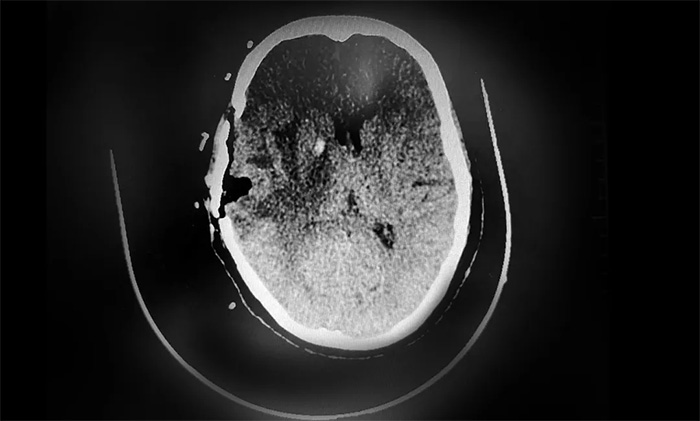

▲ CT復(fù)查示,腫瘤已被切除

根據(jù)初步病理檢測(cè)報(bào)告,送檢的樣本為顳葉轉(zhuǎn)移癌,結(jié)合病史及免疫組化,符合乳腺癌轉(zhuǎn)移。后續(xù),盧云鶴博士將根據(jù)分子病理檢測(cè)結(jié)果,為患者制定實(shí)施包括靶向治療等多學(xué)科聯(lián)合的個(gè)體化綜合治療方案,改善患者生存狀態(tài),延長(zhǎng)生存期。